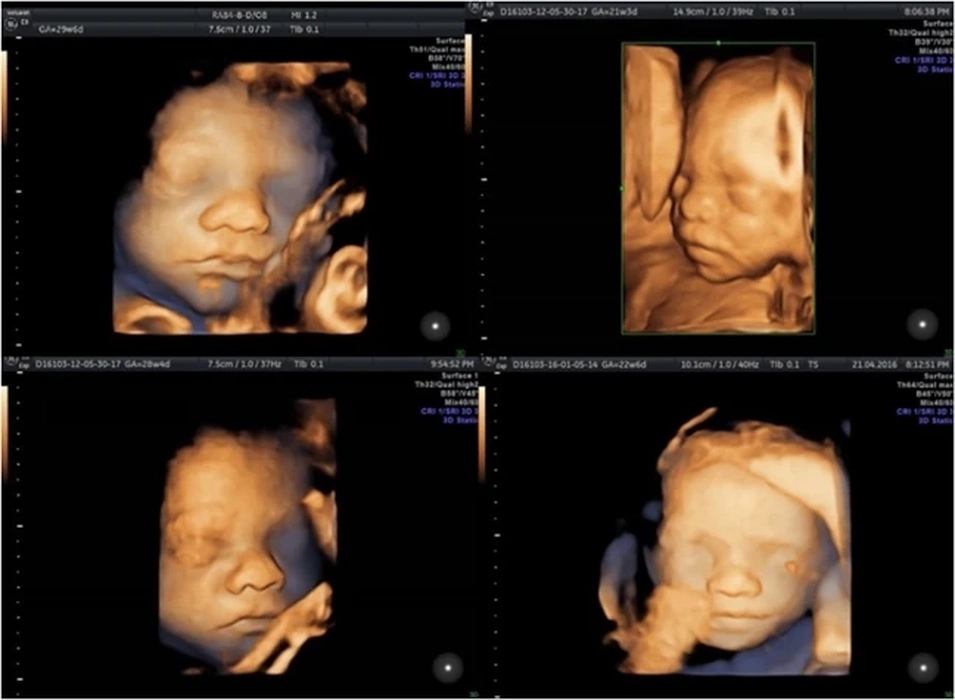

Ce preț are o morfologie fetală în trimestrul 2? Iată ce presupune examinarea, dar și care sunt factorii care influențează costul acesteia!

Pentru multe viitoare mămici, una dintre cele mai importante investigații din timpul sarcinii este ecografia morfologică din trimestrul al doilea